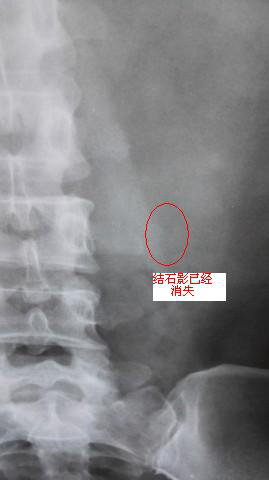

碎石后